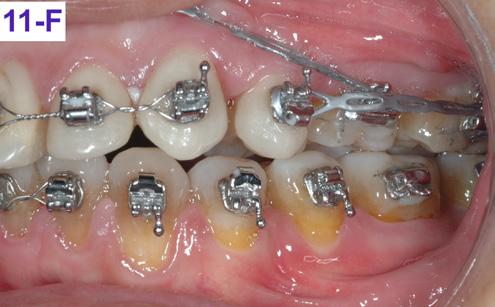

After re-bracketing, the treatment continued with the progression of the arch wires: a .014 NiTi, a .018 NiTi, a .019x025 “V” Force -3 and the final arch wire a .018x.025 SS. These final arch wires were left for three months. After this time, the esthetics, TMJ, airway, occlusion and alignment were evaluated. The patient reported that he was satisfied, and very happy with the result (Figure 11-A, B, C, D, E, F).9

11A: Pre-debracketing, lateral view

FIG. 11C: Pre-de-bracketing, lips in repose

FIG. 11D: Pre-debracketing, posed smile

FIG. 11E: Pre-debracketing, right lateral view

FIG. 11F: Pre-debracketing, left lateral view